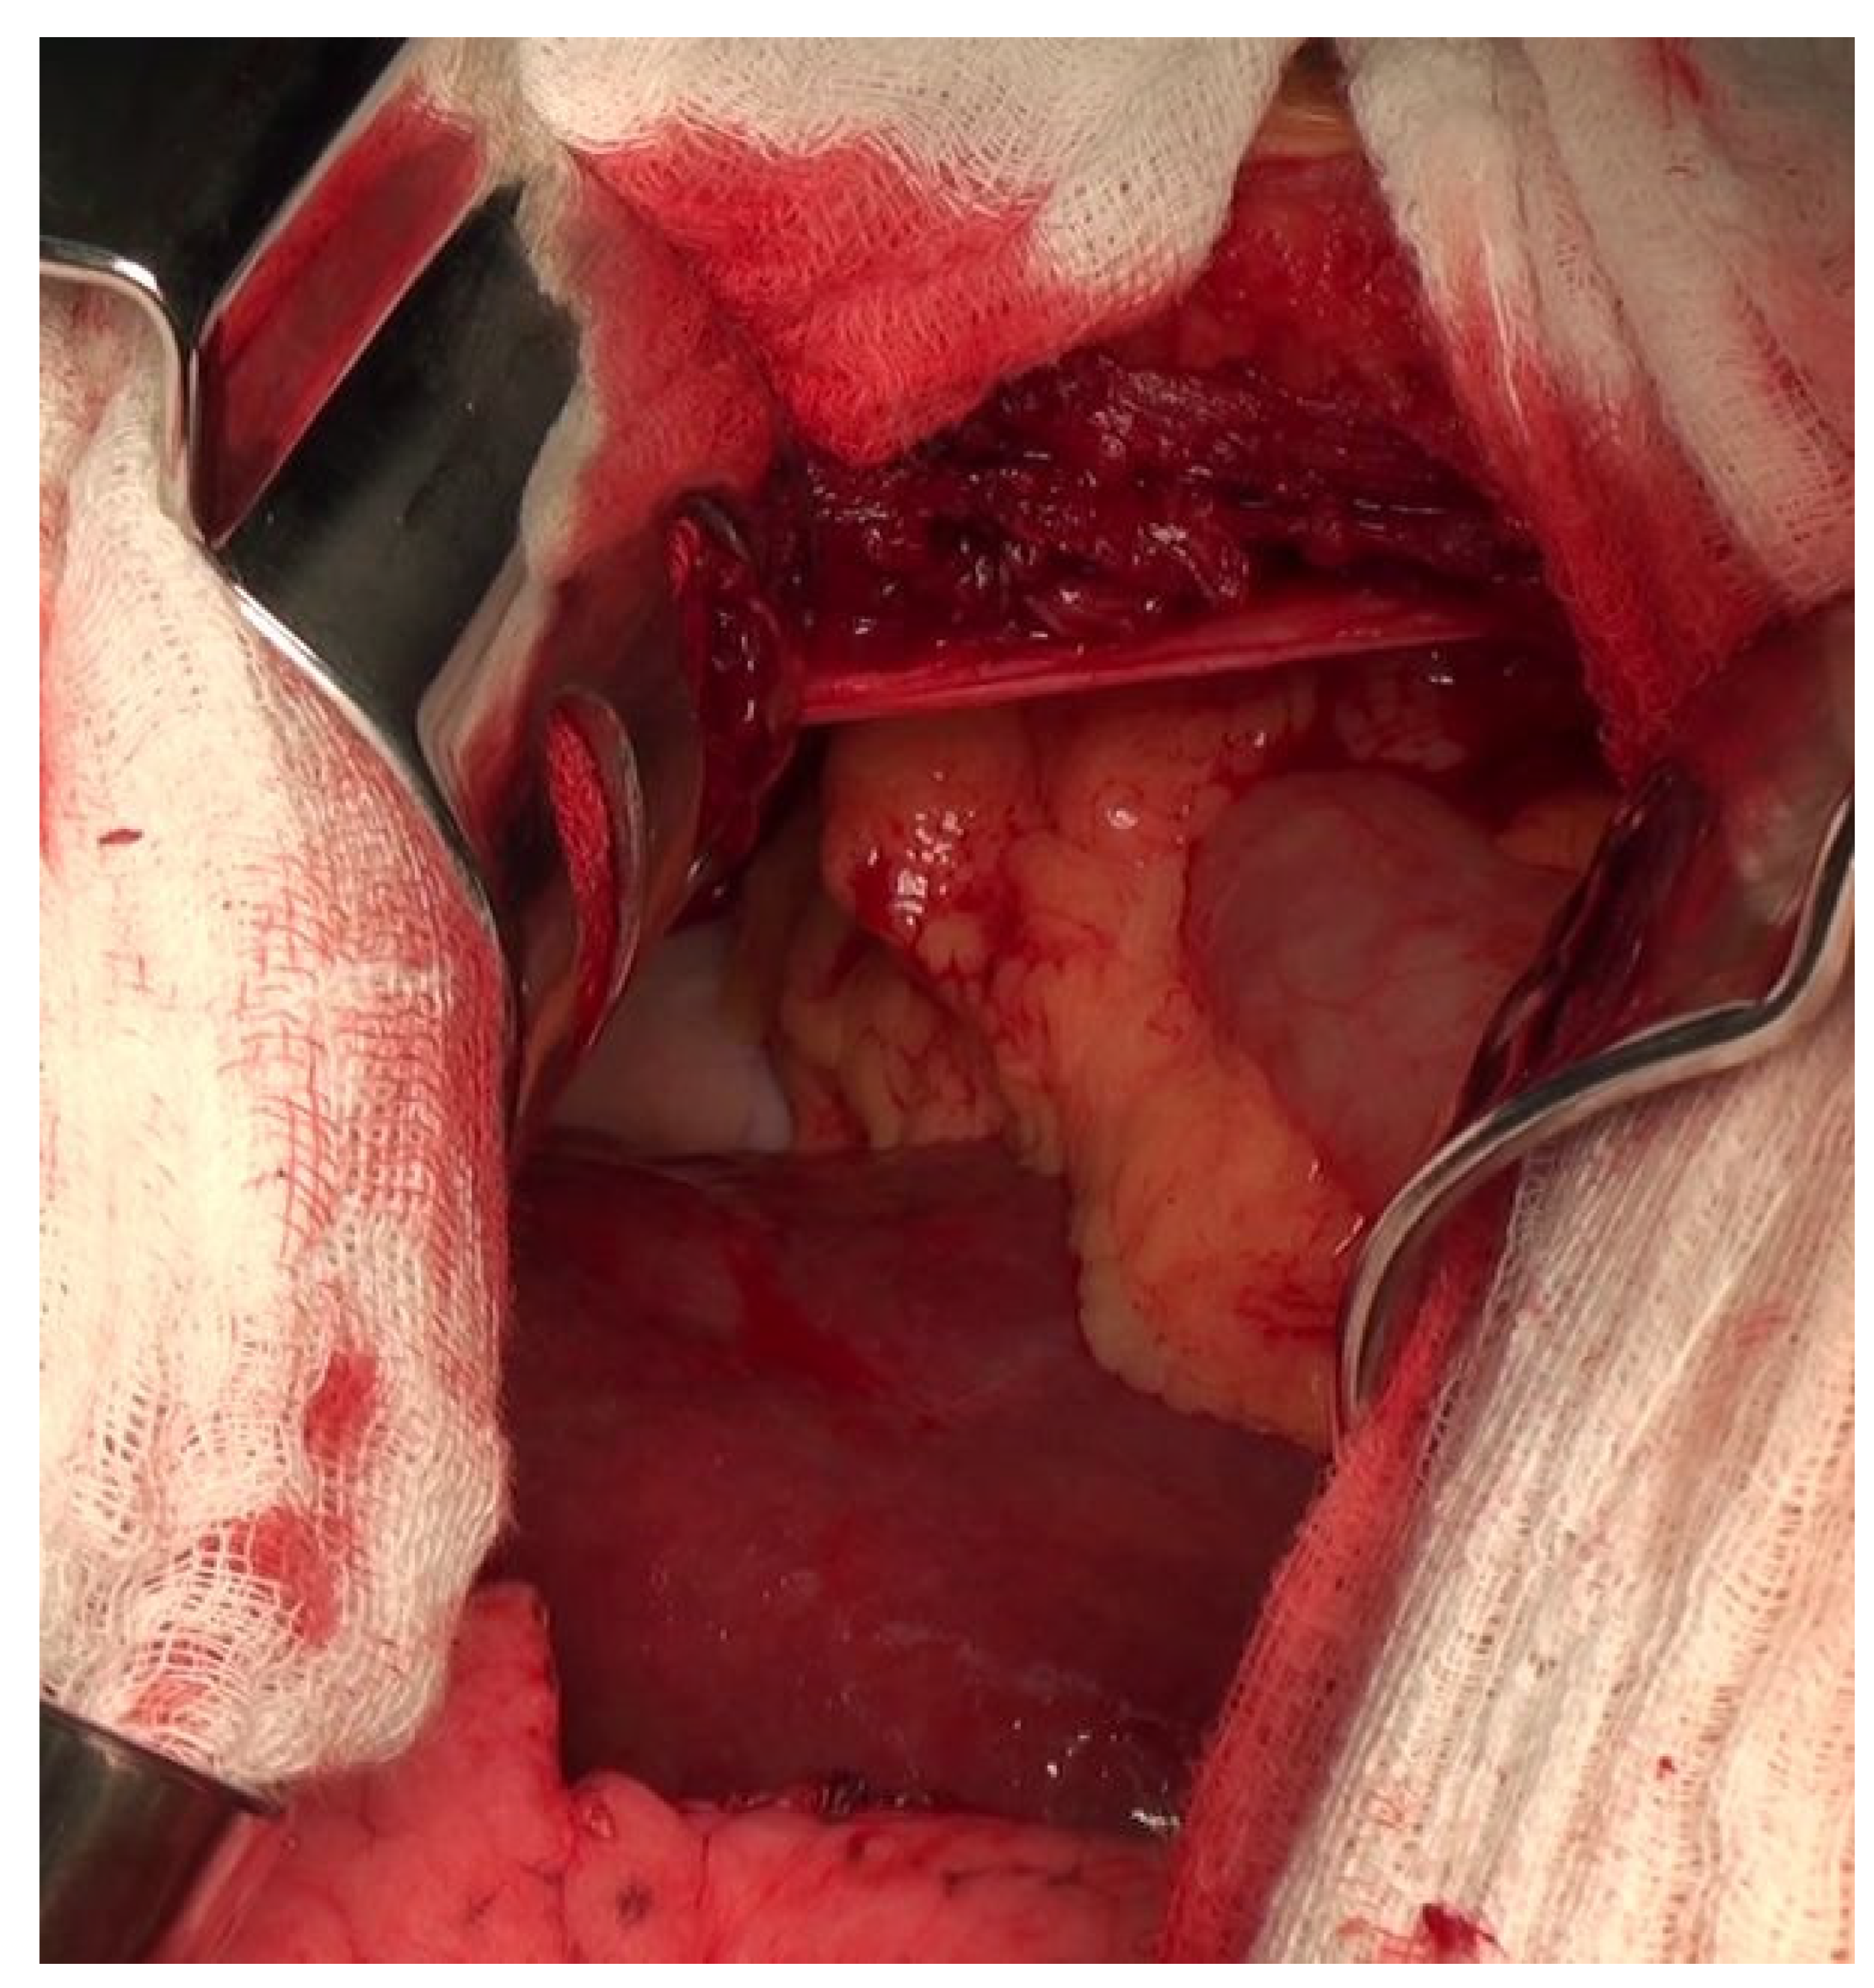

Diaphragmatic Liver Herniation after Radiofrequency Ablation of a Secondary Liver Tumor